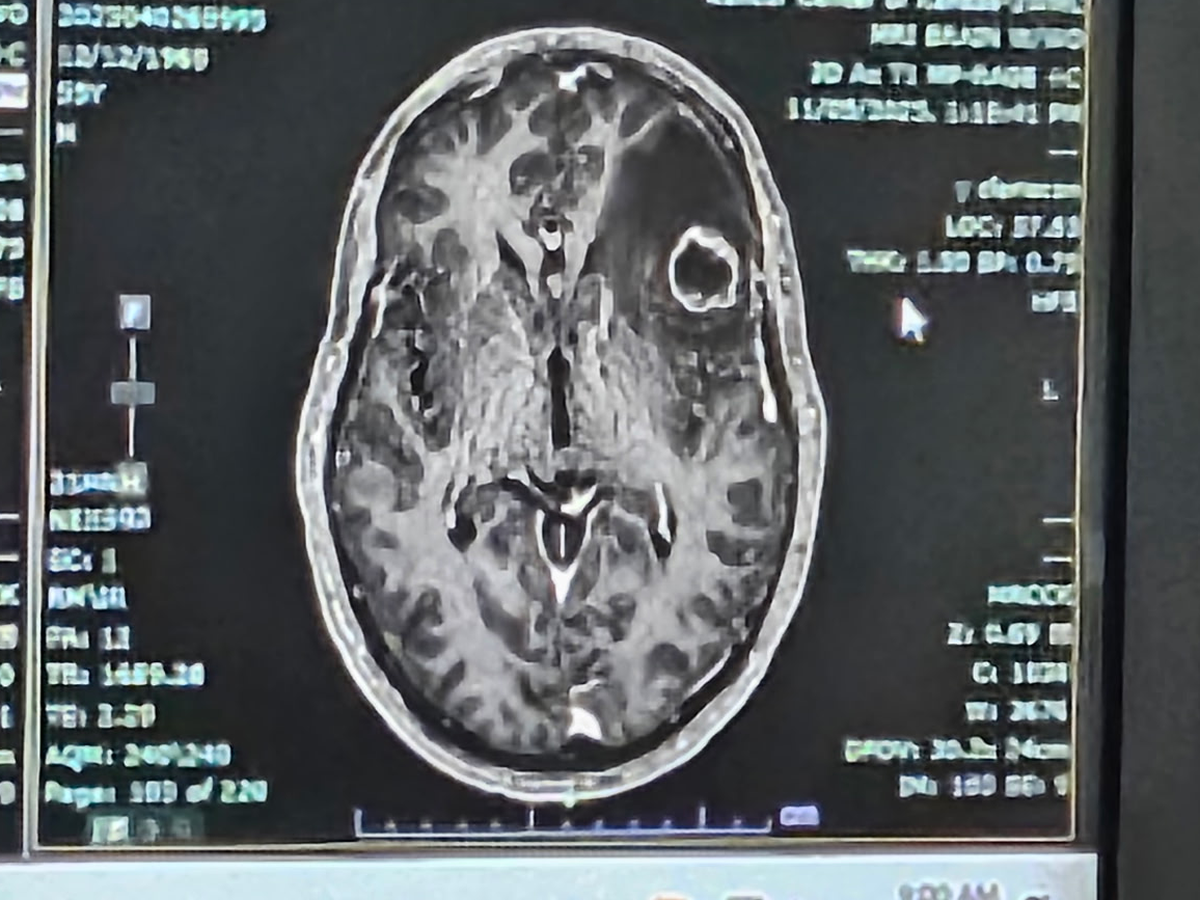

My father was diagnosed with cancer in March 2024. He has had a massive tumor on his left lung, pressing into nerves causing nerve damage and multiple brain tumors. We found out 4 weeks ago that he has a new tumor on his brain twice as big as his first one, causing swelling and memory loss.